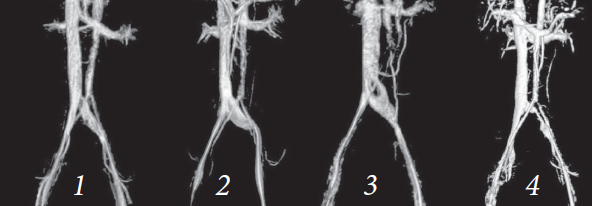

При обработке данных МРТ нижней полой вены и сосудов малого таза с 3D-реконструкцией, определяющих не локализацию, а выраженность подвздошной компрессии, мы пришли к решению о целесообразности выделения четырех стадий этого заболевания [16] (рис. 2).

Рис. 2. Стадии синдрома подвздошной венозной компрессии (синдрома Мея – Тюрнера) по данным МРТ нижней полой вены и сосудов малого таза с 3D-реконструкцией по А.А. Капто (2018): 1-я стадия — компрессия левой общей подвздошной вены; 2-я стадия — компрессия левой общей подвздошной вены с ее дилатацией; 3-я стадия — компрессия левой подвздошной вены со смыканием стенок сосуда в центральной его части и с ее дилатацией; 4-я стадия — выраженное и протяженное сужение просвета левой общей подвздошной вены

Fig. 2. Stages of the ileal venous compression syndrome (May–Thurner Syndrome) according to MRI of the vena cava inferior and pelvic blood vessels with 3D reconstruction according to A.A. Kapto (2018): stage 1 – compression of the left common iliac vein; stage 2 – compression of the left common iliac vein with its dilatation; stage 3 – compression of the left iliac vein with the closure of the vessel walls in its central part and with its dilatation; stage 4 – pronounced and extended narrowing of the left common iliac vein lumen